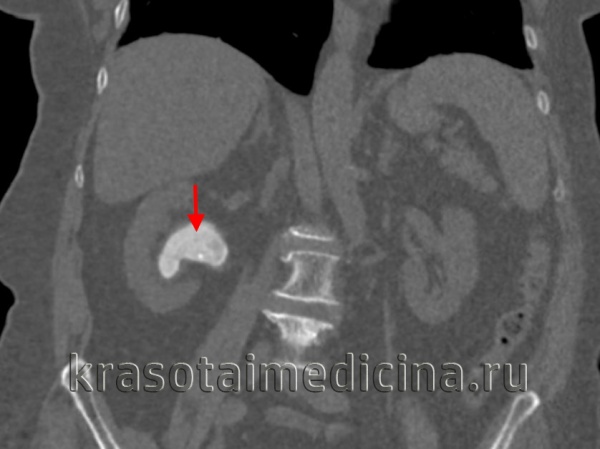

б) Спиральная компьютерная томография (КТ) без контрастирования позволяет эффективно диагностировать камни почек и мочеточников. К ее преимуществам относятся: отсутствие необходимости в применении контрастного вещества, быстрота выполнения и возможность выявления не только кальциевых, но также и уратных, и цистиновых камней.

- КТ почек. Компьютерная томография является "золотым стандартом" диагностики, поскольку позволяет увидеть конкременты любых размеров и плотности. При необходимости урологическое обследование дополняется радиоизотопной нефросцинтиграфией.

КТ ОБП и забрюшинного пространства. Плотные конкременты в нижних чашечках с обеих сторон. (фото Вишняков В.Н.)